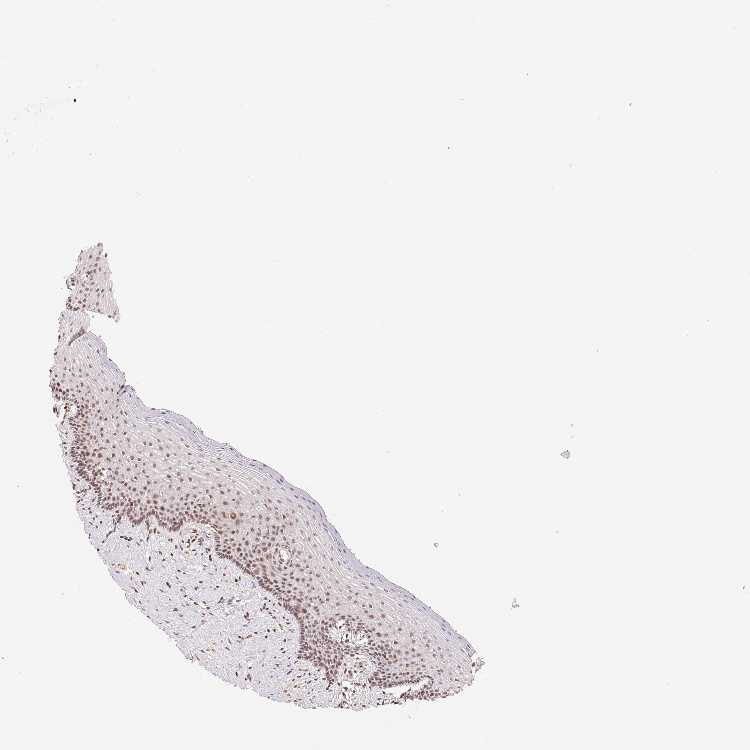

TISSUE PRIMARY DATA VAGINA Show tissue menu

VAGINA - Antibody stainingi

Antibody staining in the annotated cell types in the current human tissue is reported as not detected, low, medium, or high, based on conventional immunohistochemistry profiling in selected tissues. This score is based on the combination of the staining intensity and fraction of stained cells.

Each image is clickable and will lead to virtual microscopy that enables deeper exploration of all samples and also displays staining intensity scores, fraction scores and subcellular localization as well as patient and tissue information for each sample.

Antibody HPA063708Antibody HPA064435Antibody CAB010297

Squamous epithelial cells Not detectedMediumLow